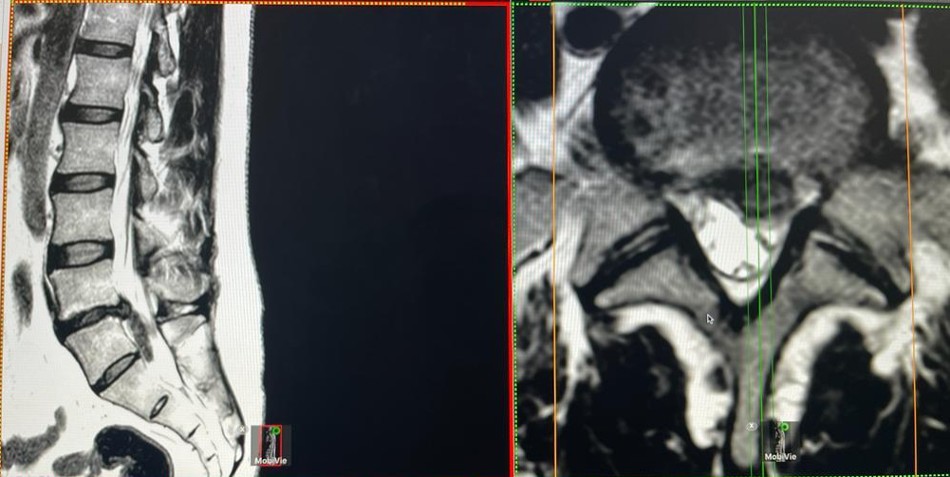

Diagnóstico: La Resonancia Magnética (RM) es de elección para el diagnóstico de la hernia de disco lumbar, se identifica la hernia, características y nivel de compresión de la raíz nerviosa. La Tomografía Computarizada (TC) también puede ser útil, aunque su imagen no es tan nítida para las partes blandas.

• RM lumbar: Es la prueba de elección, ya que proporciona información detallada sobre estructuras óseas (aunque menos definida que la TC) y partes blandas como el ligamento amarillo, discos intervertebrales y quistes sinoviales.